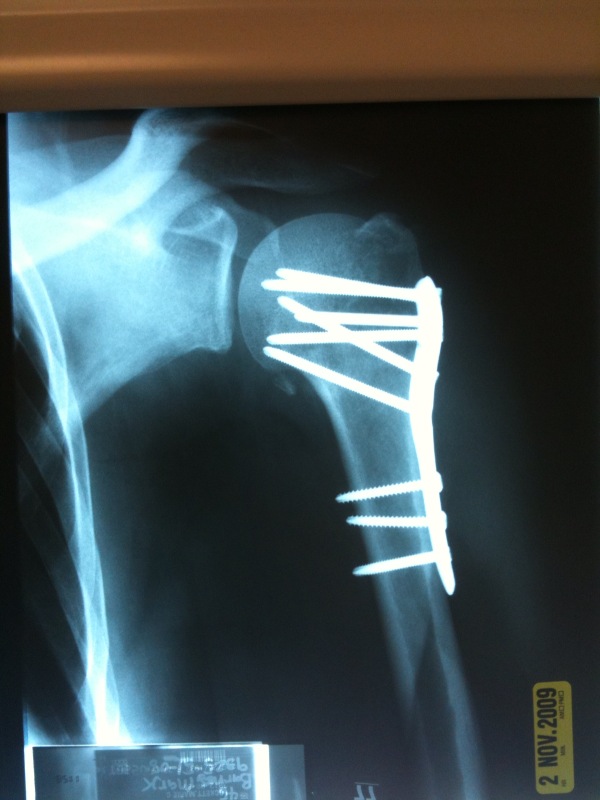

Here is pic from todays Xray.

mark screwed.jpg |

It looks like your bones are lined up nicely. How are your tendons and ligaments?

Alignment does appear pretty good. At the same time that kinda looks like some barbaric torture device. Hope it all grows together nice and smooth.

It all stays in! Unless the bone doesn't get proper blood flow. Will know in six months. Worst case, bad blood flow to the bone, they will take the whole thing out and replace with a fake ball and upper arm.

Seems to be healing nicely. No tendon or nerve damage.